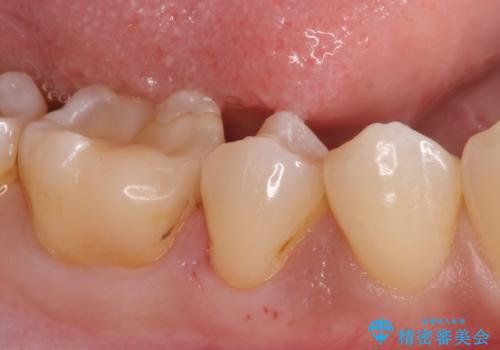

- 歯が欠けて、そこに食べ物が詰まるとのことで来院されました。

虫歯が大きく進行していました。

顕微鏡下で丁寧に虫歯を取り除き、セラミックインレーによる修復治療を行いました。